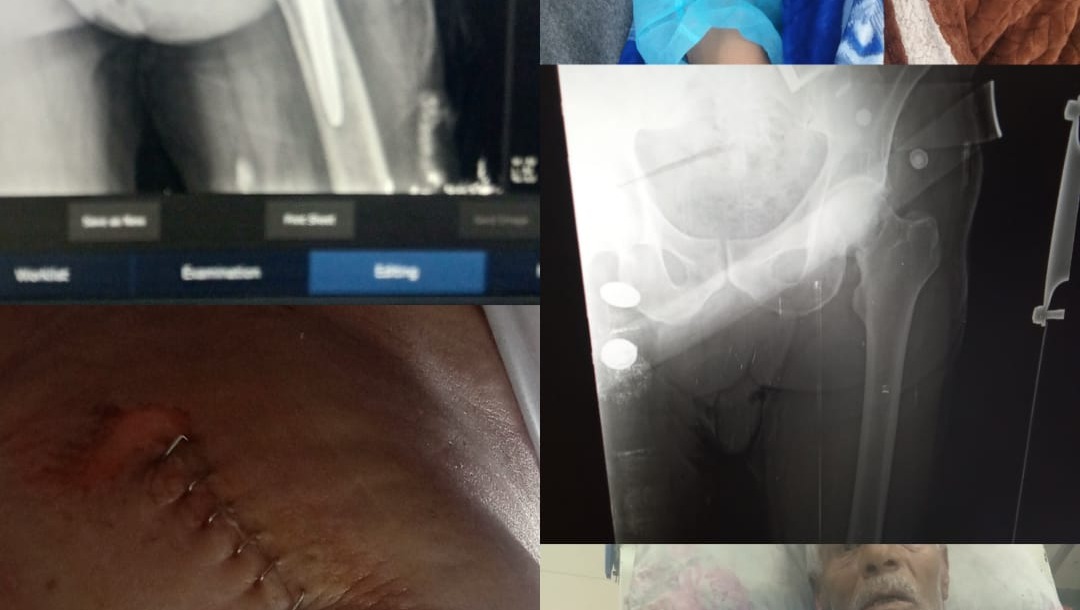

Our tent does not protect us from the freezing cold, rain, or wind. Most of my family members are injured, and we have already lost loved ones as martyrs. Every day is a fight to stay warm, fed, and alive.

It is about securing tents that can protect us from the winter cold, providing food and clean water, and obtaining basic medical care for the injured.